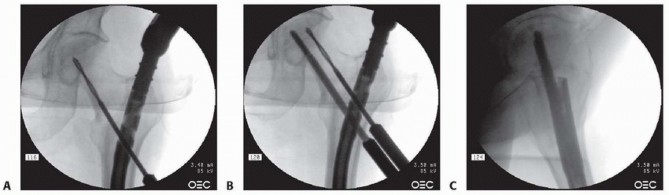

D. Channel reamer insertion through entry portal tool for soft tissue protection. E. AP radiograph of trajectory for medial trochanteric portal. F. Lateral radiograph of correct anterolateral portal with channel reamer. (A: Courtesy of Smith & Nephew, Inc.) Insertion of the guidewire too deeply will constrain the reamer usually into a varus fracture reduction position. This is because the flexibility of the wire and the lateral approach vector of the hip will always place the wire in a varus position when nailing in a supine position. One of the real advantages of the lateral position is allowing a more direct vector approach for the guidewire. A cannulated rigid reamer, preferably with modular end-cutting capability (TriGen), approximating the proximal nail geometry diameter, is introduced over the guidewire through the protective sleeve ( TECH FIG 3D). The rigid reamer or channel reamer is directed toward a point projected in the center of the medullary canal just distal to the region of the lesser trochanter ( TECH FIG 3E). The reamer is advanced in stepwise fashion while confirming maintenance of trajectory. After the reamer has been inserted about 20 mm, its trajectory is confirmed with a lateral C-arm view. The reamer should be directed along the anterior cortex of the proximal femur. The insertion of the reamer can be adjusted during reaming to approximate the position described and is most helpful in avoiding a varus position of the proximal femur. Once the canal is reamed in such a fashion, the distal femur is adjusted with the fracture table to allow correct neck-shaft angulation. The reamer is inserted until it reaches the medullary canal just below the region of the lesser trochanter ( TECH FIG 3F). The inner reamer is removed and the outer reamer is maintained for protection of the proximal reamer during the next ste 3. ##

A fracture reducer (TriGen) or similar curved cannulated device is inserted through the retained channel reamer to the fracture site and threaded through the fracture site into the distal fragment intramedullary canal, with manipulation in appropriate planes to align the fracture ( TECH FIG 4A). A long guide rod is inserted to the knee if a long nail is desired, confirming that the wire does not impinge on the anterior cortex distally. Preferably, the guide rod should be inserted to the old physeal scar and centered on AP and lateral Carm views ( TECH FIG 4B). The reducer is removed and the guidewire position is maintained with an obturator proximally. Length is checked with an appropriate ruler, allowing for fracture distraction and nail final position. The diaphyseal region is reamed up to 1 mm over the desired nail size (up to 2 mm for excessive anterior bows) ( TECH FIG 4C). The proximal expansion of the nail should have already been reamed with the entry portal reamer, but the surgeon should always confirm diameters. The channel reamer is removed and the selected nail is inserted ( TECH FIG 4D). For long trochanteric nails, it is helpful to rotate the nail 90 degrees anteriorly during the first half of the nail insertion to minimize hoop stresses in the proximal femur. After partial insertion, the nail is rotated to the anticipated anteversion required for femoral head fixation. The last 5 cm of the nail is inserted after releasing distraction sufficient for fracture apposition, maintaining correct rotational alignment. Most commercial guides use reference marks to align with the femoral head on the lateral C-arm view. These same guides may be used for C-arm verification of correct depth of insertion to allow optimal femoral head fixation.